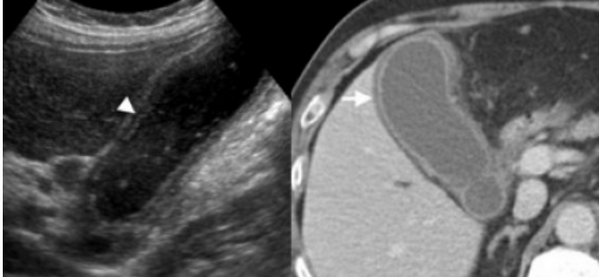

(Слева) На поперечной трансабдоминальной сонограмме в ямке желчного пузыря визуализируется эхогенная структура изогнутой формы с акустической тенью — изменения, характерные для «фарфорового» желчного пузыря.

(Справа) На сонограмме визуализируется стенка желчного пузыря с диффузно повышенной эхогенностью и объемное образование в области его дна. Задняя стенка желчного пузыря различима, в отличие от эмфизематозного холецистита или множественных камней, заполняющих желчный пузырь. При патоморфологическом исследовании были обнаружены интрамуральные кальцинаты, признаки хронического холецистита и аденокарциномы желчного пузыря.

4. УЗИ признаки фарфорового желчного пузыря:

• Существует несколько возможных вариантов:

о Эхогенная структура изогнутой формы в ямке желчного пузыря с плотной акустической тенью:

- Акустическая тень «чистая»; в отличие от эмфиземы эхогенные очаги или «грязная» тень отсутствуют

- Комплекс «стенка-сигнал-эхо» не определяется, как это бывает при желчном пузыре, заполненном камнями

о Биконвекситальные обызвествления изогнутой формы в стенках желчного пузыря с возможностью визуализации его задней стенки:

- В случае эмфизематозного холецистита или, если желчный пузырь заполнен камнями, его задняя стенка не визуализируется

о Грубые включения извести в стенке ЖП с акустической тенью